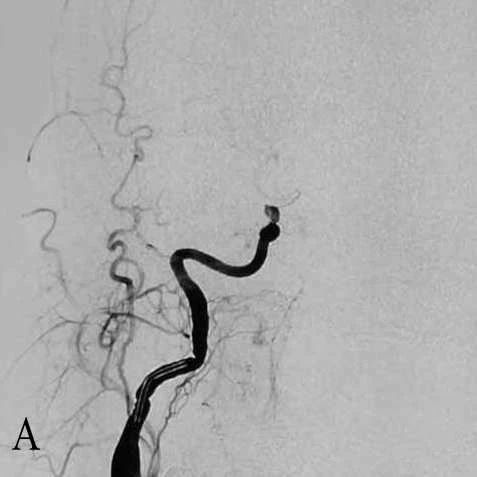

A:右侧ICA造影正位示后交通动脉以远闭塞